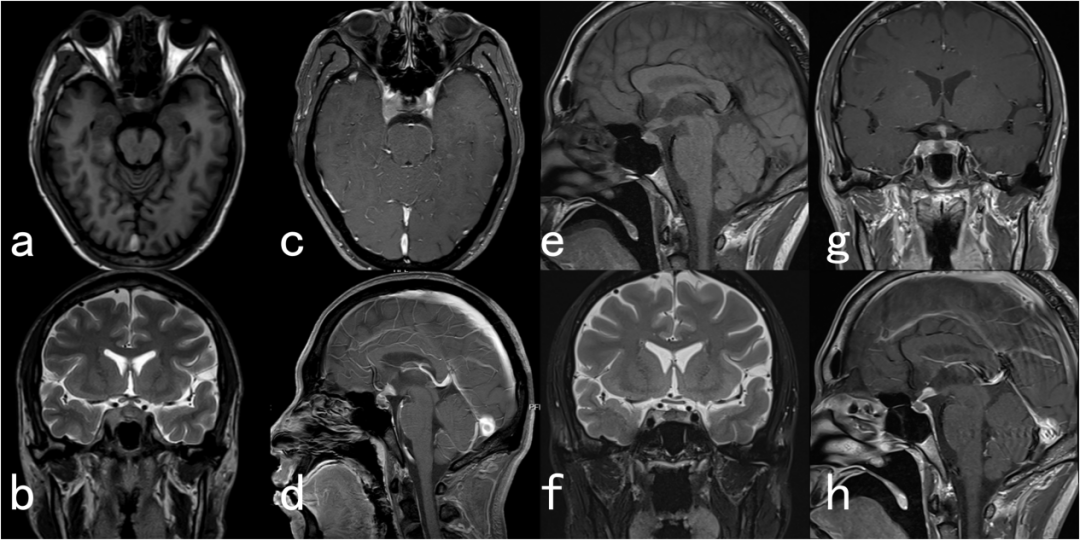

垂体柄阻断综合征